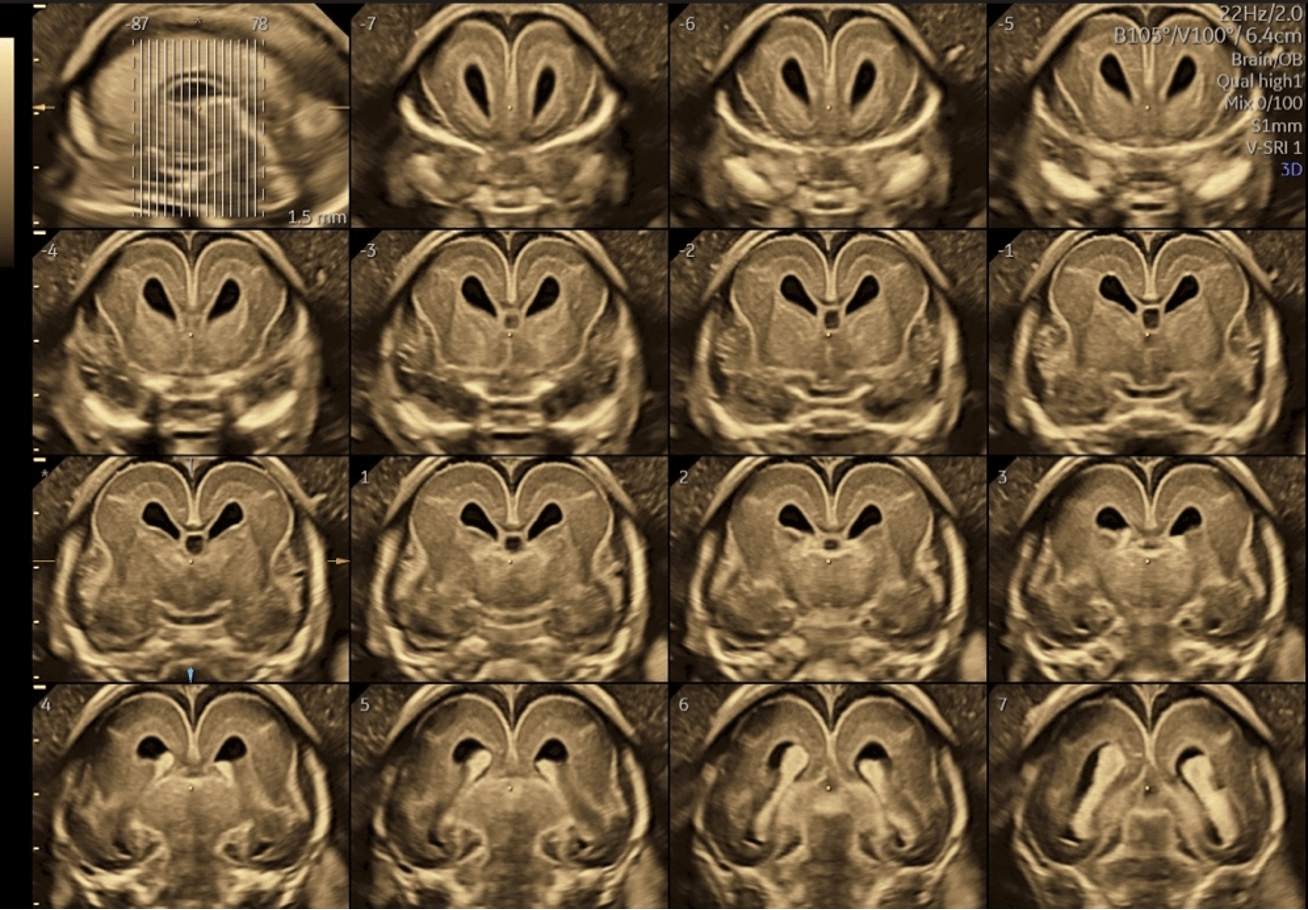

方法:高精度3D経膣脳神経超音波による脳の詳細計測

結果:先天異常を持つ胎児群を複数のグループに分類し、サブプレートの発達パターンを比較分析した結果、グループ間で明確な発達の違いを確認。

クリフム出生前診断クリニックでは、胎児ドック全例において定量的・定性的な胎児脳評価を行う「胎児脳ドック」を標準実装しています。一般的な妊婦健診では実現困難な高精度胎児脳評価を通じて、人間にとって最も重要な器官である脳の発育を胎児期から詳細に診断しています。これまでは「生まれて育っていく過程でしかわからない」とされていた神経発達を胎児期より詳細に観察し、胎児脳研究で世界をリードする存在です。